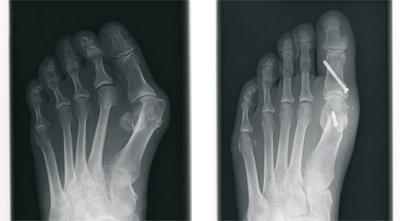

Buckling-fallen arches (flat feet) by children

During childhood flatfoot buckling is initially a perfectly normal and even necessary for the rolling foot position when walking. Only at a certain severity it is called a real deformity of the foot. The position can improve during the years automatically.

A pathological deformity can cause pain around the ankle and Achilles tendon and in the area of the knee joint. Even symptoms in the back or the hip may result. First of all a basic medical examination is appropriate but a further treatment not often necessary. In severe deformity or relevant symptoms should be a thorough investigation, including x-ray examination in a standardized technique.

For treatment the first steps are insoles and foot exercises, if this is not enough of a surgical procedure must be taken into consideration.

For this a modern minimum invasive Procedure, the so-called arthroereisis is available for some years. Through a small incision of no more than 2 cm, a special invented screw is inserted into the lower ankle. Important soft tissues or joints wont be stiffened or destroyed.

Flatfoot raising comes by the the screw. After two weeks a normal ist load possible. The Screw can be removed after 2-3 Years, the improved foot positions remains.